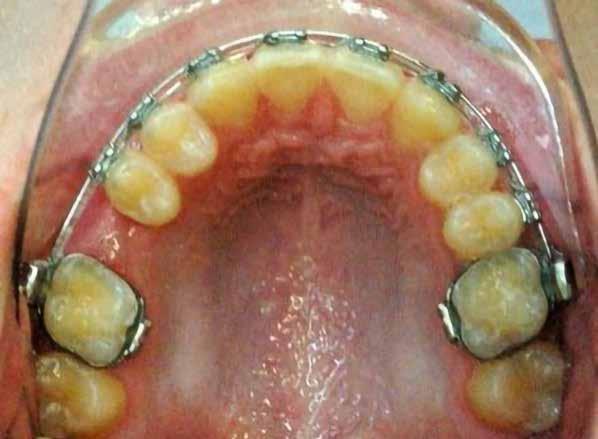

A vegyes fogazati kezelési célok a fogívek tágítása és a mandibula meziális irányú növekedésének a biztosítása volt. Fontos, hogy az ilyen típusú készülékeket nem csak éjszaka, hanem napközben is – amennyit csak lehet – hordani kell a minél hatékonyabb működés érdekében. A 18 hónapos első fázisú kezelésnek köszönhetően az alap kezelési célok megvalósultak, sikerült a class 1-es okklúziót beállítani (4-7. képek).

Abban az esetben, amikor az első fázisú kezelési célok elérése megtörtént, de még nem törtek elő a maradó fogak az első moláristól az első molárisig – mintegy passzívan, csak éjszakánként hordva –, tovább folytatjuk a funkcionális kivehető készülék viselését.

Esetünkben 18 hónap után a maradó fogazat előtörése megtörtént, így rögtön folytathattuk a fogszabályozást.